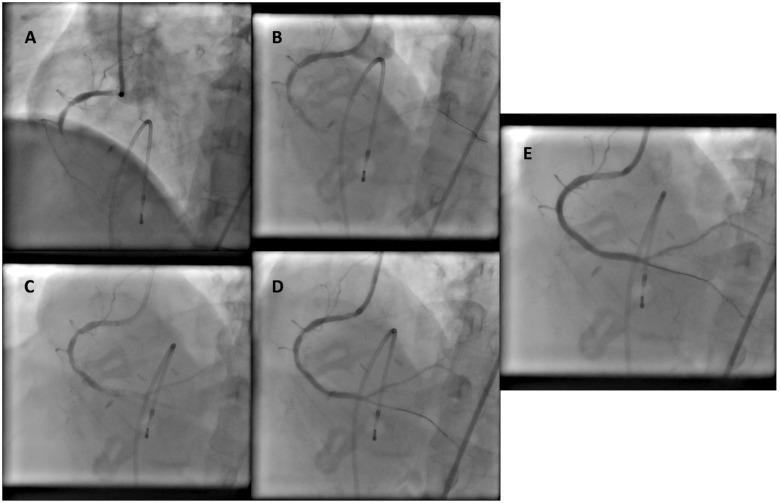

This series demonstrates the use of intracoronary thrombolysis in the setting of large coronary thrombus, bifurcation lesions with vessel size mismatch, diffuse thrombosis without underlying plaque rupture, and improving coronary flow to allow vessel wiring and proceeding to definitive revascularization.

本系列病例展示了冠状动脉内溶栓在冠状动脉大血栓、血管大小不匹配的分叉病变、无潜在斑块破裂的弥漫性血栓形成以及改善冠状动脉血流以允许血管穿线并进行确定性血运重建等情况下的应用。